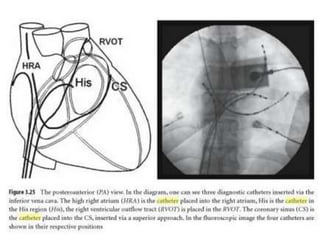

Standard Catheter Electrodes •High RA – Quadripolar – Femoral route – Tip - superolateral – near SVC/RA junction

• 27.

Standard Catheter Electrodes •RV apex – Quadripolar – Femoral route – Tip – as close to RV apex as possible

• 28.

Standard Catheter Electrodes •Coronary Sinus – Decapolar – Easiest access via SVC - IJV/SCV route

• 29.

Standard Catheter Electrodes •His Bundle – Quadripolar; 2-2-2 – Femoral route – Tip – straddles tricuspid annulus in its superior portion

• 30.